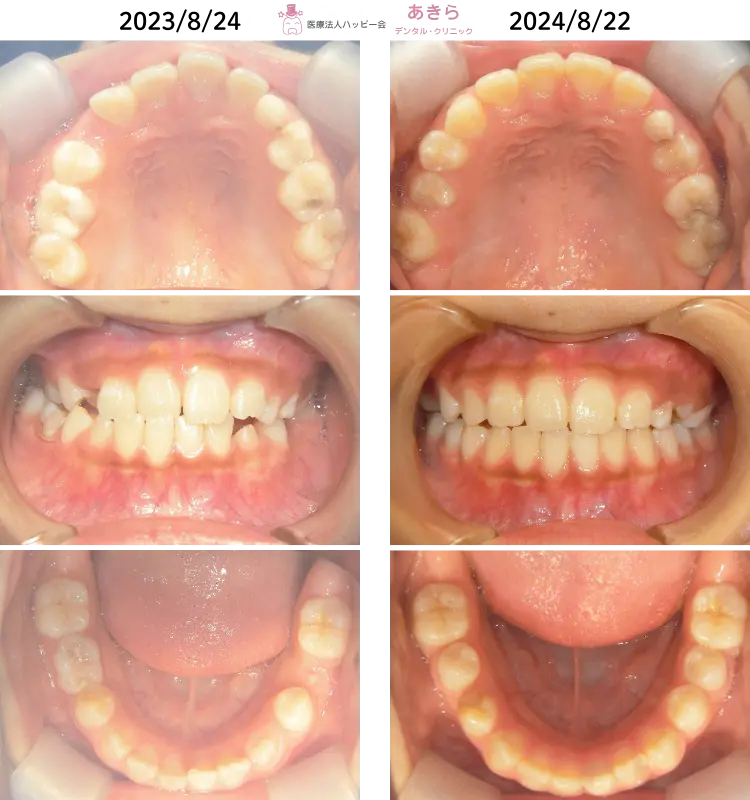

SH療法

SH療法-症例-No.012-外傷歯を伴う叢生(凸凹)の矯正症例

山形市の歯医者「あきらデンタル・クリニック」のSH療法の症例をご紹介します。 SH… -